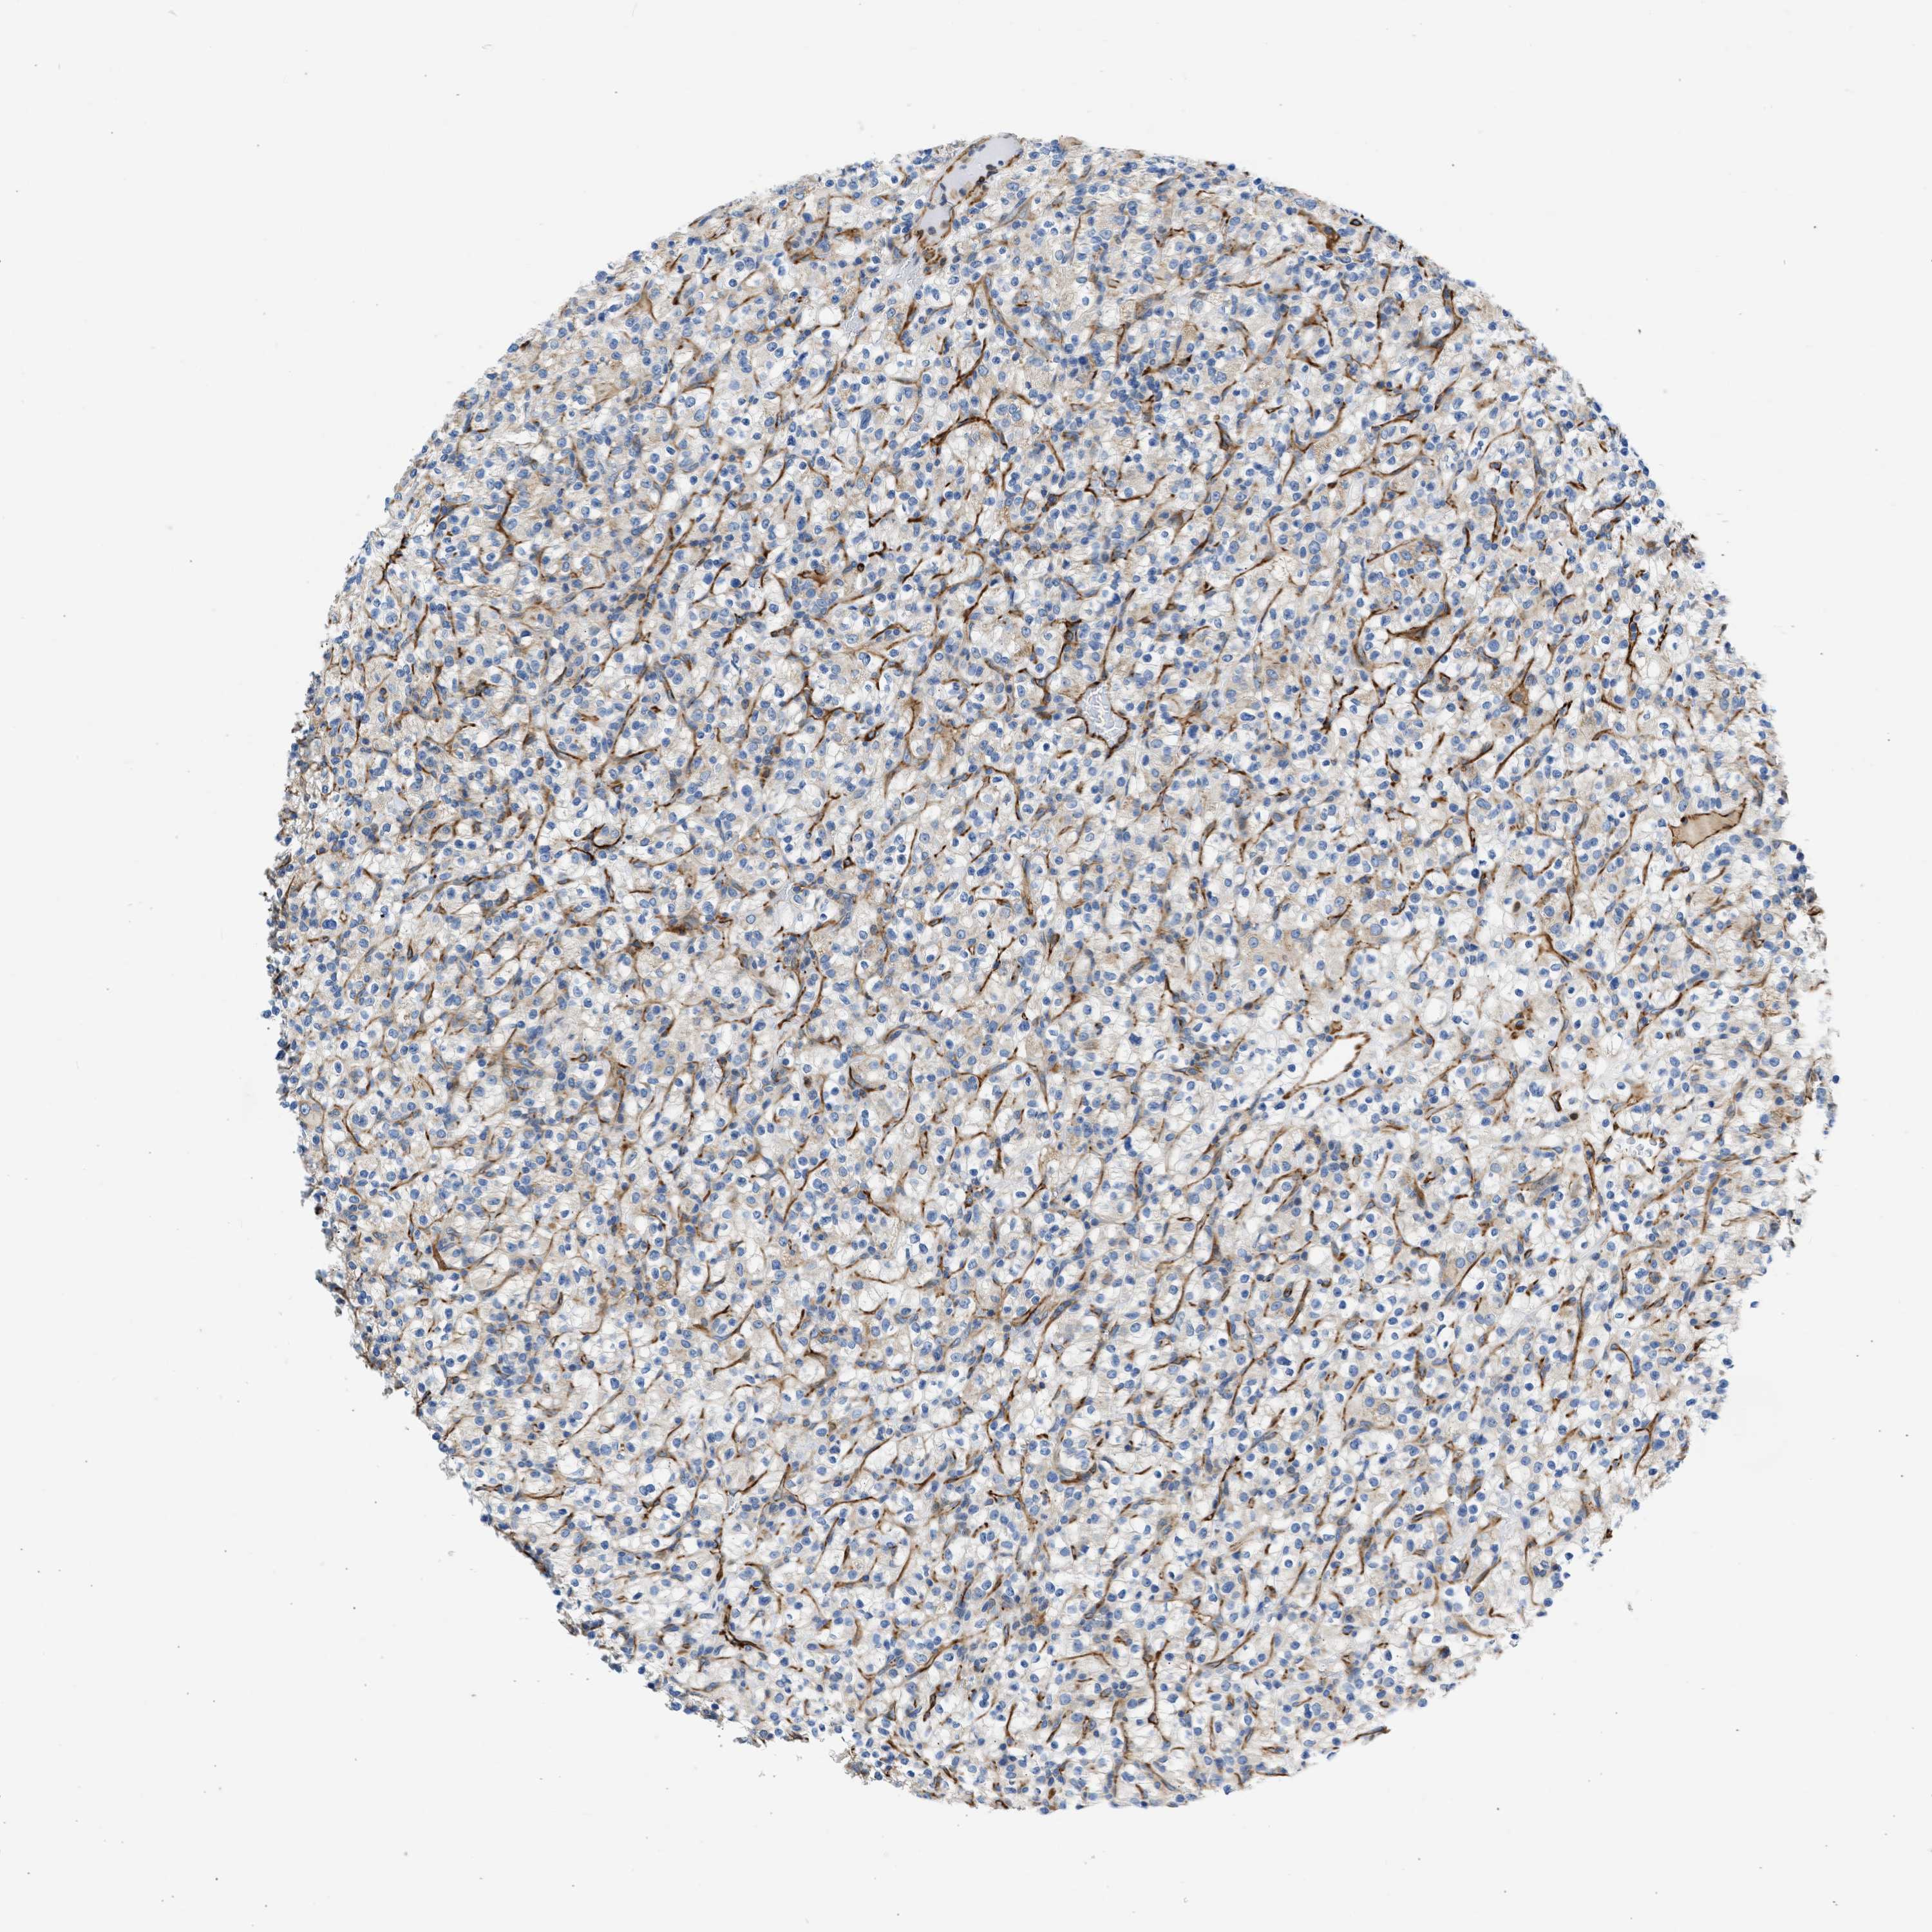

KIDNEY RENAL CLEAR CELL CARCINOMA (TCGA) - Interactive survival scatter ploti

The Survival Scatter plot shows the clinical status (i.e. dead or alive) for all individuals in the patient cohort, based on the same data that underlies the corresponding Kaplan-Meier plots. Patients that are alive at last time for follow-up are shown in blue and patients who have died during the study are shown in red.

The x-axis shows the expression levels (FPKM) of the investigated gene in the tumor tissue at the time of diagnosis. The y-axis shows the follow-up time after diagnosis (years). Both axes are complimented with kernel density curves demonstrating the data density over the axes. The top density plot shows the expression levels (FPKM) distribution among dead (red) and alive patients (blue). The right density plot shows the data density of the survived years of dead patients with high and low expression levels respectively, stratified using the cutoff indicated by the vertical dashed line through the Survival Scatter plot. This cutoff is automatically defined based on the FPKM cutoff that minimizes the p-score. The cutoff can be changed by dragging the vertical line or by entering a cutoff value in the square labeled "Current cut-off".

Under the Survival Scatter plot the p-score landscape (black curve; left axis) is shown together with dead median separation (red curve; right axis). Dead median separation is the difference in median mRNA expression between patients who have died with high and low expression, respectively. It is calculated as follows: median FPKM expression of dead patients with high expression - median FPKM expression of dead patients with low expression. This is intended to aid the user in visually exploring custom cutoffs and the associated p-scores and dead median separation.

Individual patient data is displayed and can be filtered by clicking on one or more of the category buttons on the top of the page. Categories describing expression level and patient information include: high, low, alive, dead, female, male and tumor stages. The scale of the x-axis can be toggled between linear and log-scale by clicking on the "x log" button. Mouse-over function shows TCGA ID, patient information and mRNA expression (FPKM) for each patient.

& Survival analysisi

Kaplan-Meier plots summarize results from analysis of correlation between mRNA expression level and patient survival. Patients were divided based on level of expression into one of the two groups "low" (under cut off) or "high" (over cut off). X-axis shows time for survival (years) and y-axis shows the probability of survival, where 1.0 corresponds to 100 percent.

ULK4 is not prognostic in Kidney Renal Clear Cell Carcinoma (TCGA)

Best expression cut offi

: 2.15

Average pTPM 2.0

Number of samples 521